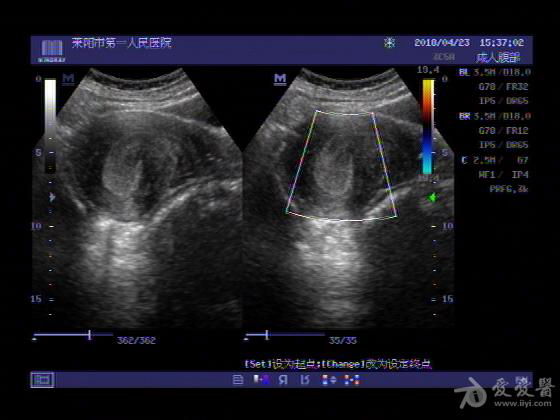

女,48岁,月经量多,两个月,一年前出现过类似现象,刮宫吃药后缓解。

超声可见:子宫内膜显著增厚,后肌壁内膜可见范围约3.27X0.90CM低回声区,CDFI显示较丰富线样血流,宫底宫腔内见类**状低回声结节。前肌壁见多发类圆形低回声结节。

超声提示:子宫内膜增厚(建议刮宫病理),子宫多发肌瘤

病理结果:内膜增生